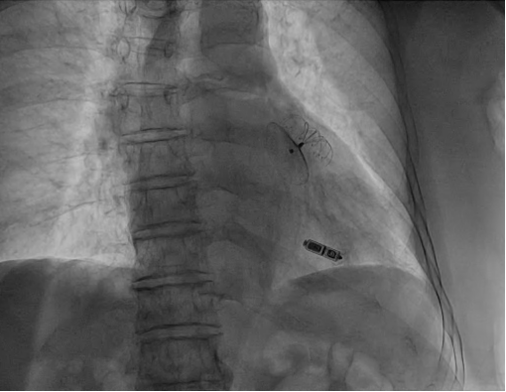

左心耳封堵器及无导线起搏器最终影像

医务团队与患者及其家属充分沟通,权衡利弊后,决定为其行一站式左心耳封堵与无导线起搏器植入术。在手术团队的精心配合下,不到一个小时就完成了一站式手术,术中左心耳封堵器效果较好,无导线起搏器电学参数理想,术后第二天患者就下床活动,恢复情况良好。